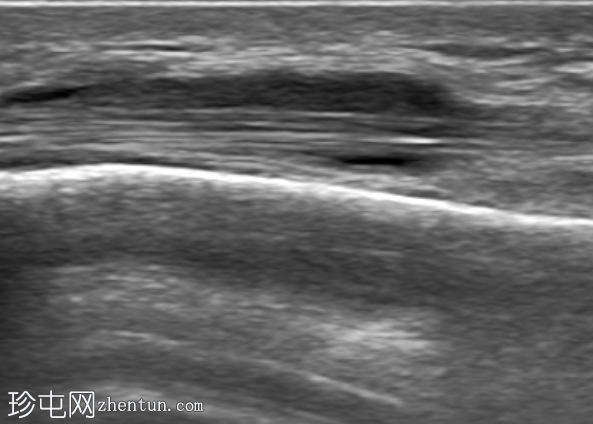

超声

纵切面

第一背侧伸肌腱鞘增厚。拇长展肌 (APL) 和拇短伸肌 (EPB) 肌腱周围可见低回声液体。受累肌腱轻度增厚。未见肌腱撕裂。邻近皮质表面完整。多普勒显示轻度血流信号增多。